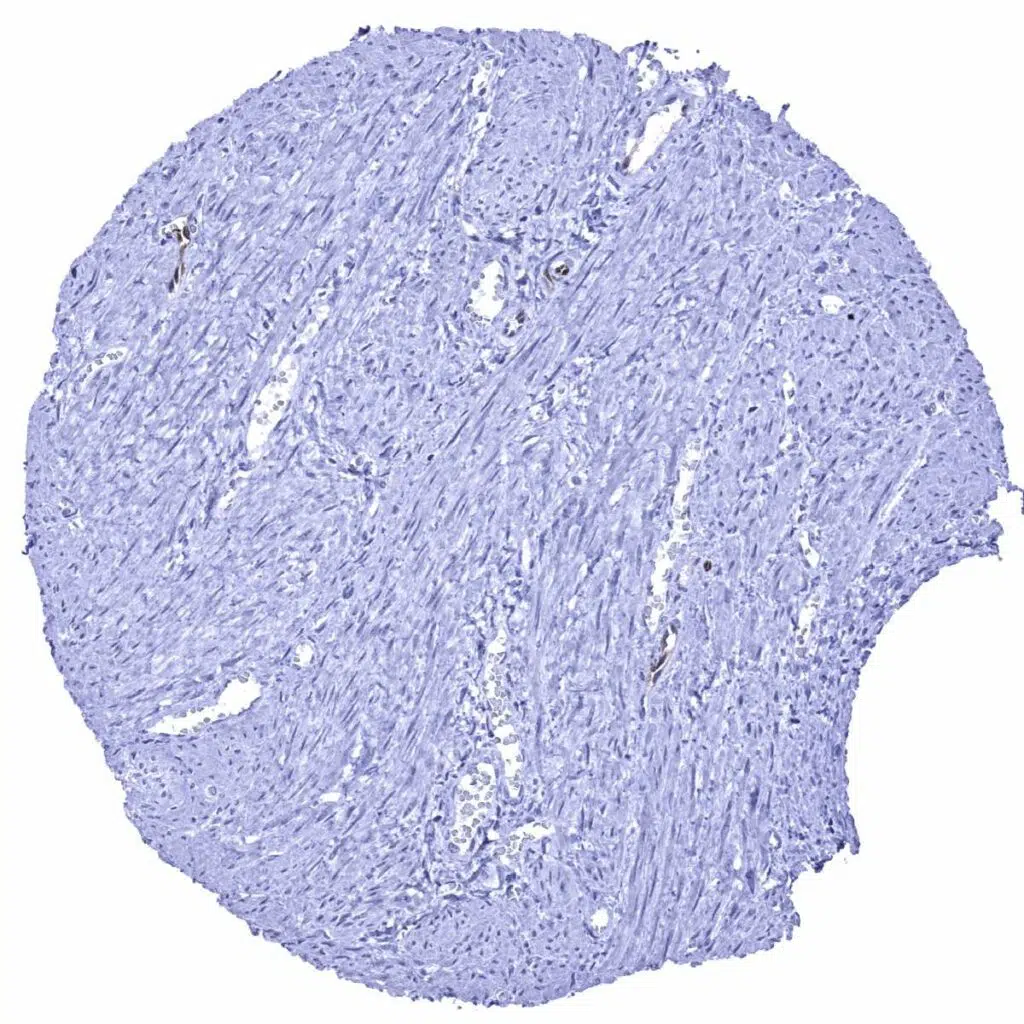

Urinary bladder, muscular wall

Uterus, myometrium – A weak GS staining is seen in few endothelial cells of small capillaries